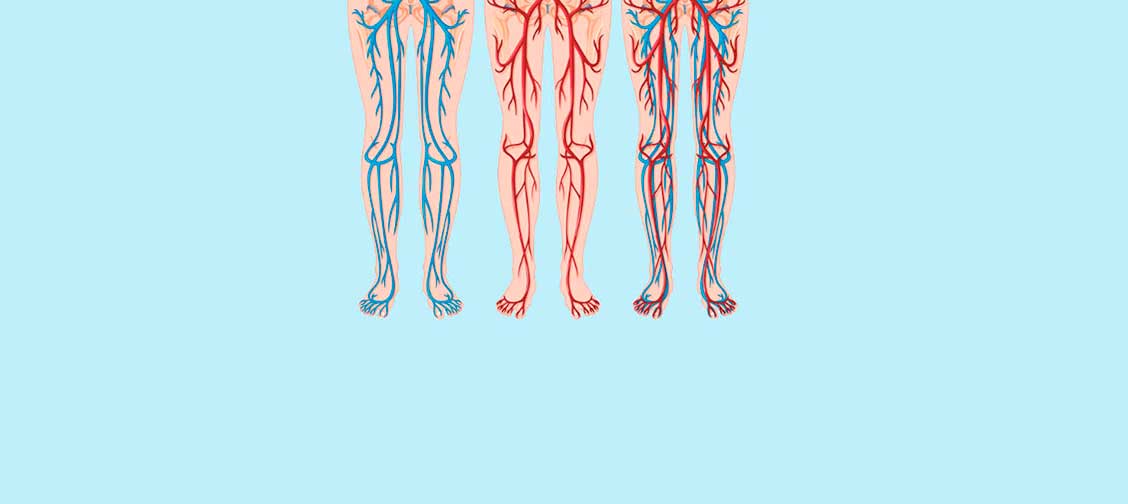

Koji je najveći organ u ljudskom telu? Malo ljudi zna odgovor na ovo. Čak i ljudi koji su studirali medicinu ponekad odgovaraju pogrešno govoreći mozak ili jetra. Neki mudriji mogu reći da je to koža. Zapravo najveći organ u ljudskom telu je vaskularni sistem.

Pokušajte da zamislite. Ako bismo spojili sve vene u ljudskom telu i izmerili ih, dužina bi im bila 100 hiljada kilometara.

Jednostavnije rečeno, dužina ekvatora je 40 hiljada kilometara. Konopac koji se sastoji od jedne ljudske vene može dva puta da omota svet.

Vene nisu samo kanali kroz koje teče krv. To je jedinstven i komplikovan organ. Svaki njihov poremećaj uzrokuje da telo razvije bolest.

Blokirane vene na nogama: Varikozne, natečene noge, osećaj težine, hladne noge, ili suprotno, peckanje u tabanima. Pukotine na koži. Poremećaji cirkulacije krvi: zaštita od bakterija je smanjena, formira se gljivična bolest. Nokti postaju deblji i oštećuje im se oblik.